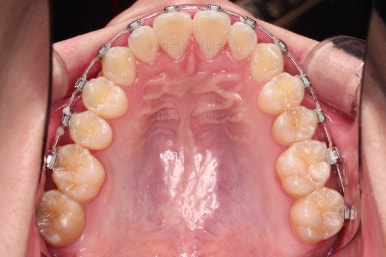

부산교정치과 초진 시 입안의 모습입니다.

앞니가 삐뚤어서 결손치아가 없었더라도 교정치료를 원하셨던 상황이었고요.

오른쪽 어금니 맞물림은 결손치아도 그렇지만 전반적인 앞뒤 차이가 있는 부정교합이 있었어요.

윗니는 가지런하게 하면서 아랫니는 초기 단계부터 뒤로 밀어주게 됩니다.

보통 철사교정을 할 때 100% 가지런해진 뒤 밀고 당기는 경우가 있는데요.

그것보다는 가능한 초기부터 가지런하게 하는 것 + 뒤로 미는 것을 병행하면 치료기간을 효율적으로 단축할 수 있답니다.